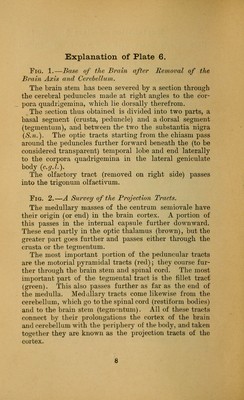

An atlas of the normal and pathological nervous systems : together with a sketch of the anatomy, pathology, and therapy of the same / Tr. and ed. (authorized) by Joseph Collins.

Credit: An atlas of the normal and pathological nervous systems : together with a sketch of the anatomy, pathology, and therapy of the same / Tr. and ed. (authorized) by Joseph Collins. Source: Wellcome Collection.